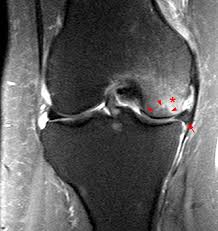

Bone Marrow Edema Edema Is Seen In Subchondral Bone As A Hyperintense Download Scientific Diagram